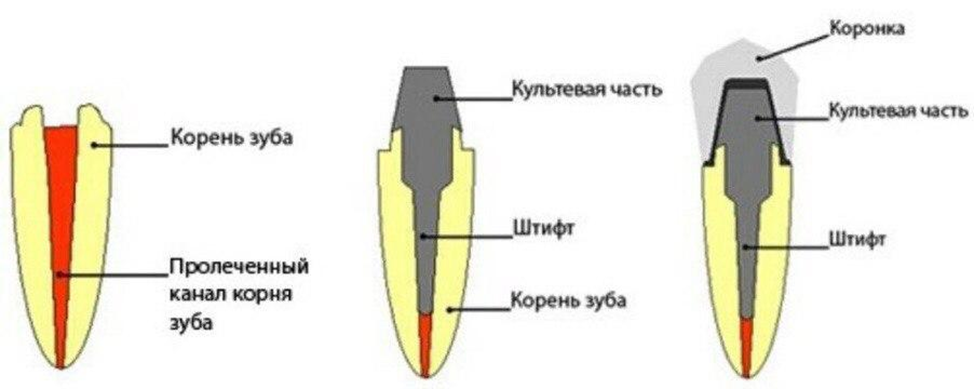

Культя зуба это

Культя зуба это 106 фото